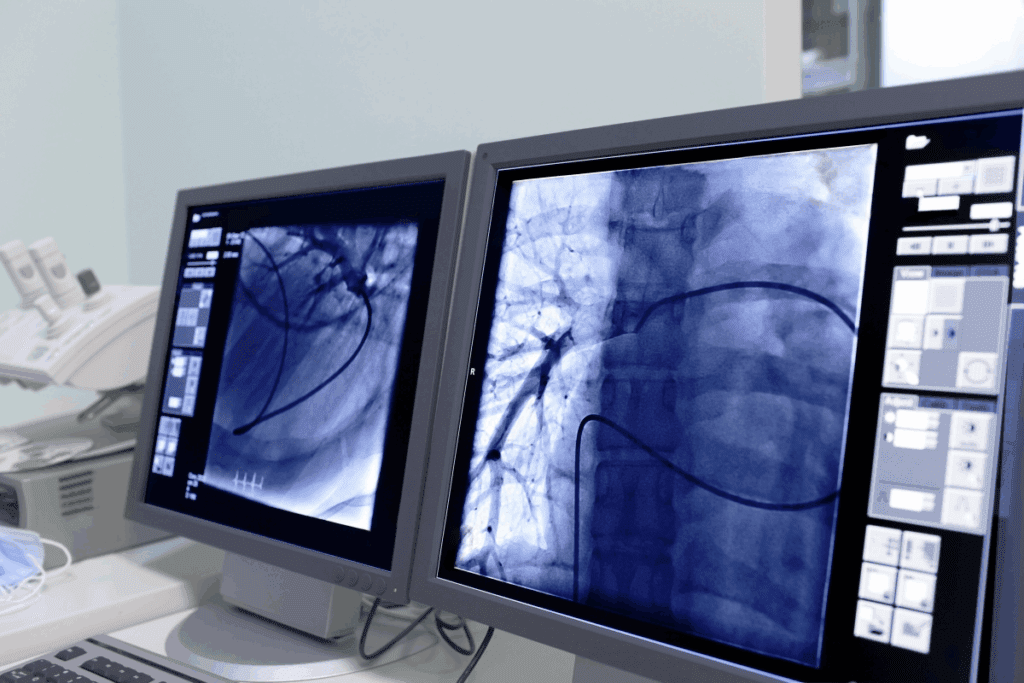

Interventional radiologists are key in diagnosing and treating complex health issues. They use advanced imaging to do minimally invasive procedures. This makes treatments safer and less invasive than traditional surgery.

Interventional radiologists use imaging to find and treat many health problems. This includes heart diseases, cancers, and stomach issues. They do things like angioplasty and tumor removal.

They use X-rays, CT scans, MRI, and ultrasound to guide their work. This makes treatments more precise and effective.